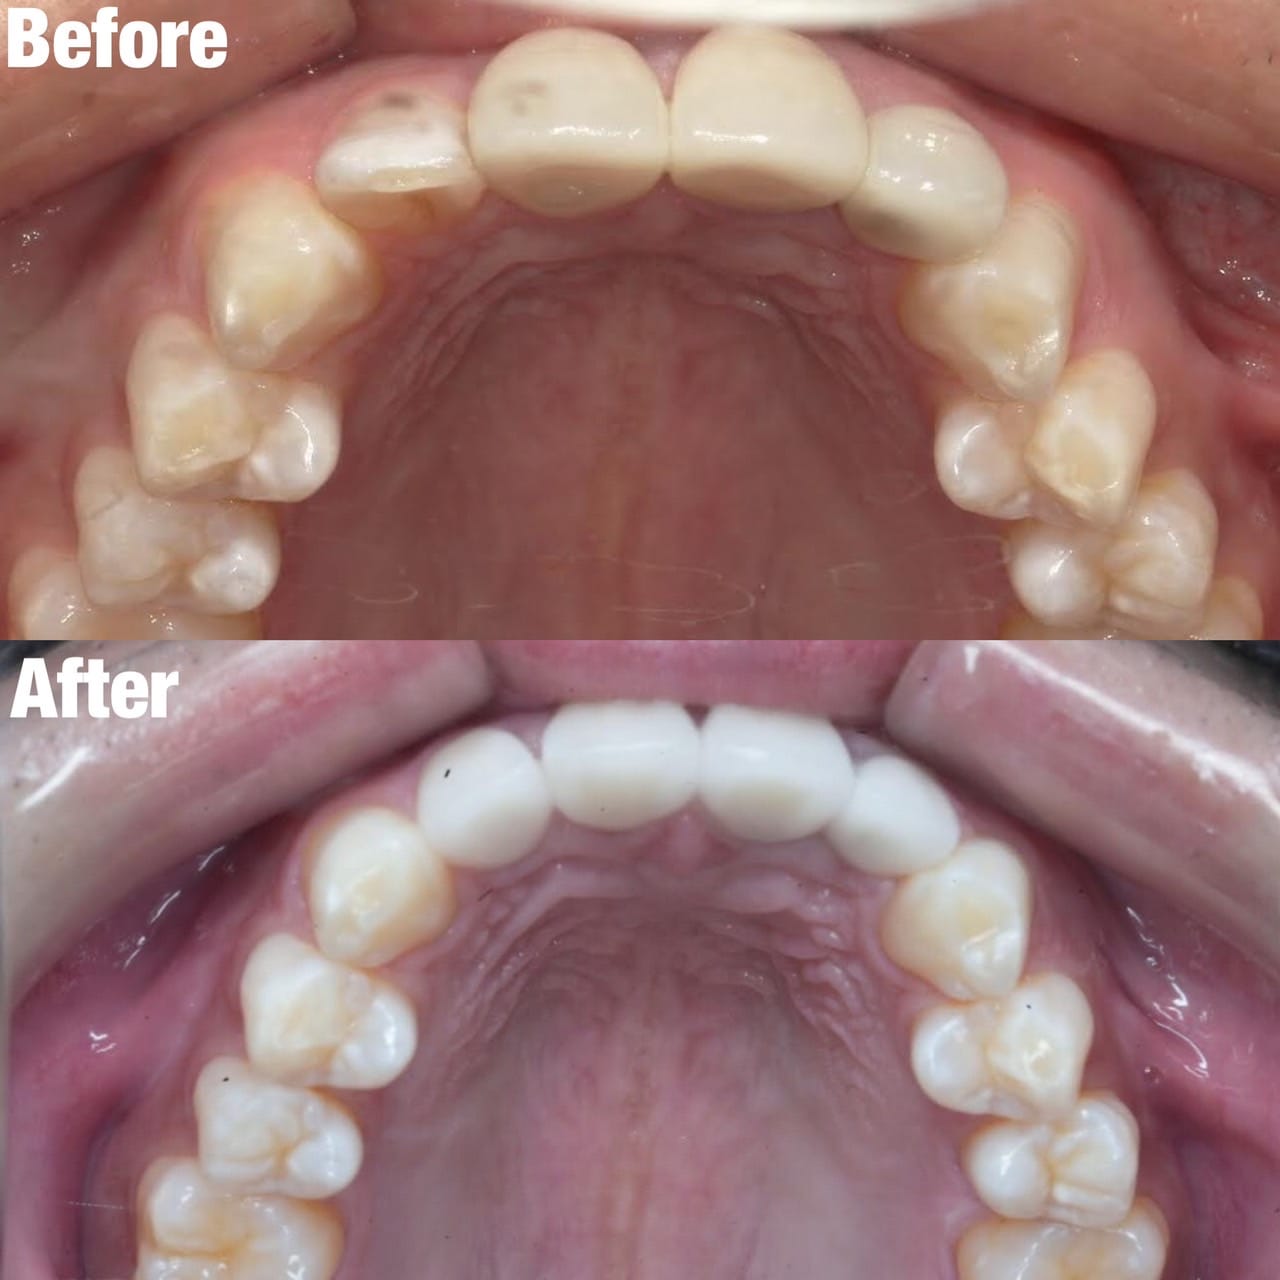

Case032

メジャーリーグでも活躍した元プロ野球選手の山口俊さんのセラミック治療を担当いたしました。

「他院で治療を受けたセラミックが欠けた」というのが主訴でしたが、よく診察するとセラミック欠けただけではなく、被せ物がしっかりと合っていないことが原因で歯茎の腫れがあり、歯石や汚れもつきやすい状態でした。また、歯列も若干歪んでいたので、この機会に全て治療いたしました。

治療後は透明感のある白さで、綺麗な歯並びになりました。また、セラミックをきちんと綺麗に削って適合よくセットしたことにより、歯茎の腫れも改善しました。

セラミックを入れた所の歯茎が腫れていて悩まれてる方はぜひご相談ください。

綺麗に削って適合よくセラミックをしてあげれば必ず改善します。